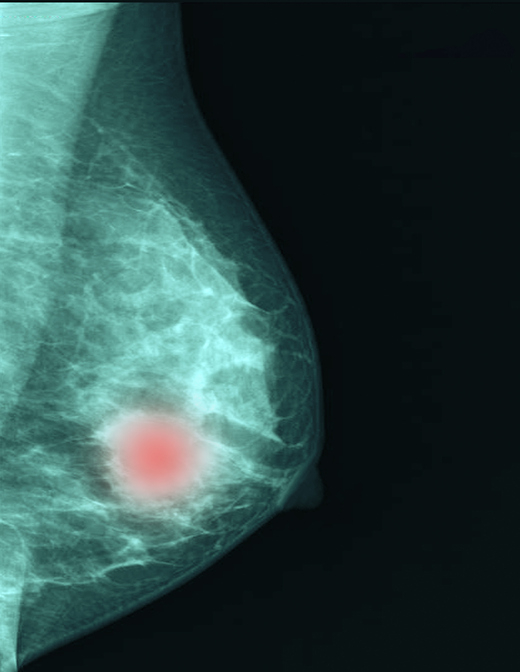

유방암 중에서도 치료가 까다롭기로 알려진 유형이 '삼중음성(Triple Negative) 유방암'이다. 그런데 이 암에서 유전자와 단백질 정보를 함께 분석하면 항암치료 효과를 정확하게 예측할 수 있다는 연구 결과가 나왔다. 환자마다 다른 치료 반응을 사전에 가늠해 개인 맞춤 치료로 이어질 수 있는 기반이 마련됐다는 점에서 주목된다.

삼중음성 유방암은 에스트로겐·프로게스테론 등 여성호르몬 수용체와 HER2 수용체가 모두 없는 형태로, 표적 항암제가 작용하는 3가지 수용체가 모두 없는 유형이라 일반 유방암보다 치료가 어렵다. 전체 유방암의 15% 수준으로 비율이 높지는 않지만, 예후가 가장 좋지 못하고 전이·재발 위험이 큰 유형이다. 다른 유방암보다 진행 속도가 빠르고 재발 위험이 크다. 수술 전 선행 항암 화학요법을 먼저 시행하는 경우가 많지만, 환자마다 치료 반응 차이가 커 예측하기가 어렵다.